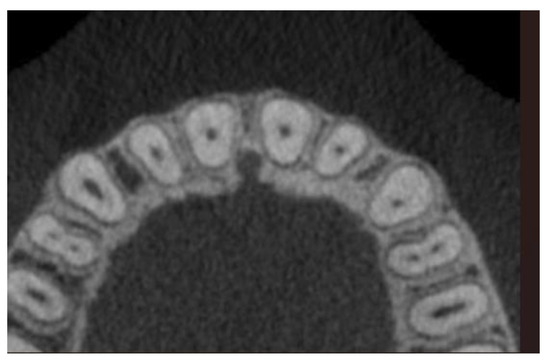

2.2. Data Acquisition and Measurements

- Horizontal plane separately for each level—L1, L2, and L3: